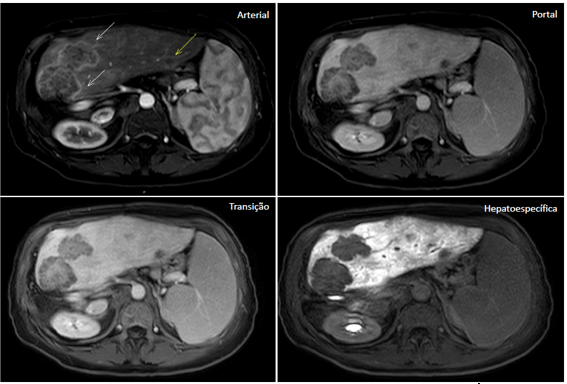

Fuente: archivo personal, en colaboración con la Dra. Ângela Caiado

Figura 2. Nódulo en la cara anterior del segmento II/III, de 1,2 cm, con realce en la fase arterial, aclaramiento precoz y sin retención en la fase hepatoespecífica.